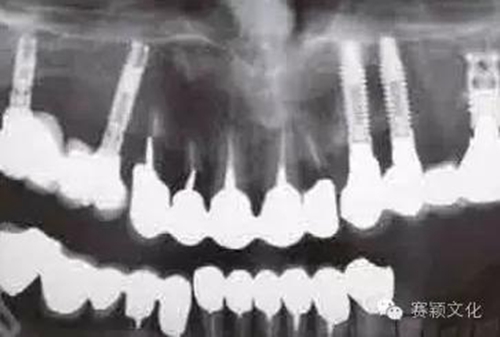

2.jpg

圖2 術(shù)前全景片

在某些特殊情況下,種植體需植入類骨質(zhì)(例如含BMP-2移植骨材料,密質(zhì)骨<15%)中,此時(shí)最好使用表面處理且粗糙的種植體。此處展示一應(yīng)用粗糙且表面處理的螺紋型種植體行拔牙位點(diǎn)的即刻種植(圖2~8)